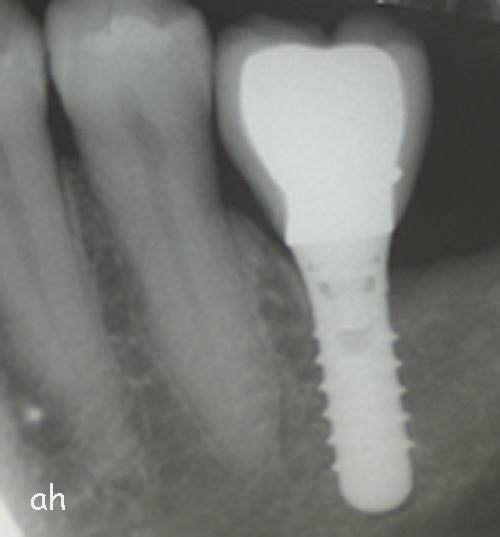

Exemple 12: Ici la pose de deux implants est envisagée, mais la hauteur d'os est insuffisante pour le deuxième implant. Le sinus (qui est une cavité creuse) est à moins de 6 mm de la surface de l'os. Idéalement il faudrait 10 mm d'os.

Exemple 12: Il faut donc relevé le sinus avec une greffe d'os avant de poser l'implant (Sinus lift).

Exemple 12: Les moignons vissés sur les implants 6 mois plus tard.

Exemple 12: Les couronnes en place.